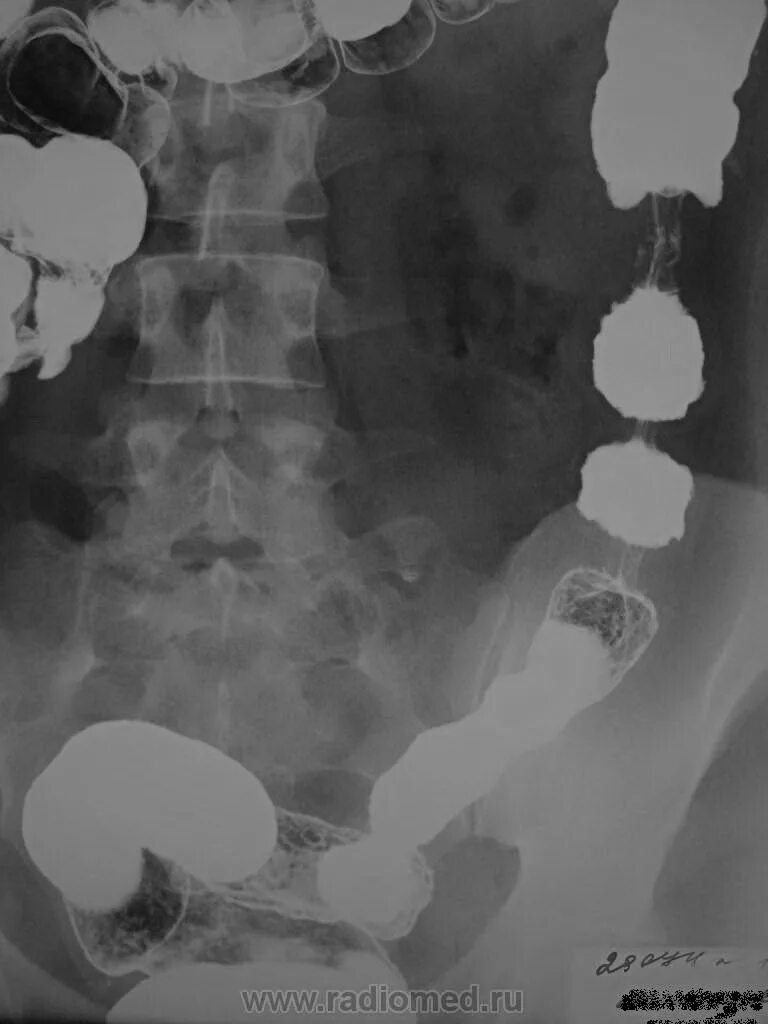

Ирригоскопия с двойным контрастированием